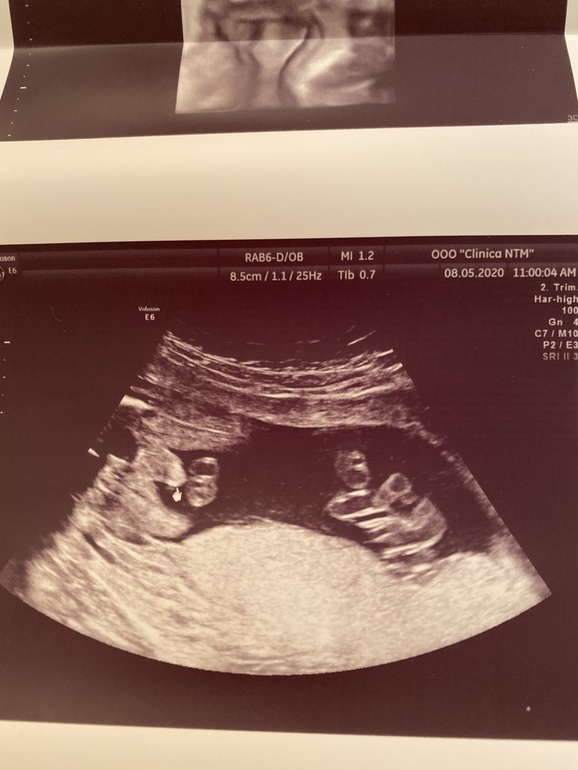

Анна Бернецкая

Девочки если вам не трудно, можете покидать фото с ваших узи , уж очень интересно для сравнения 🤨

мой мальчишка, срок 17+4